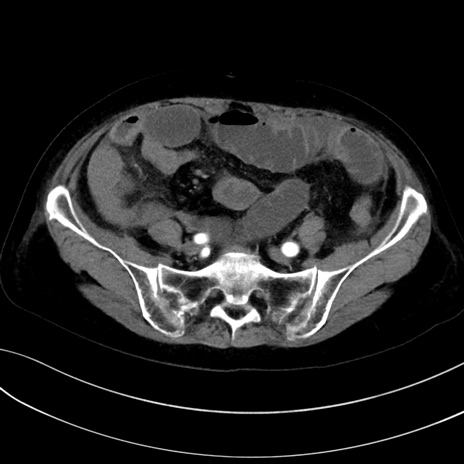

症例13 CT(横断像)1日半後